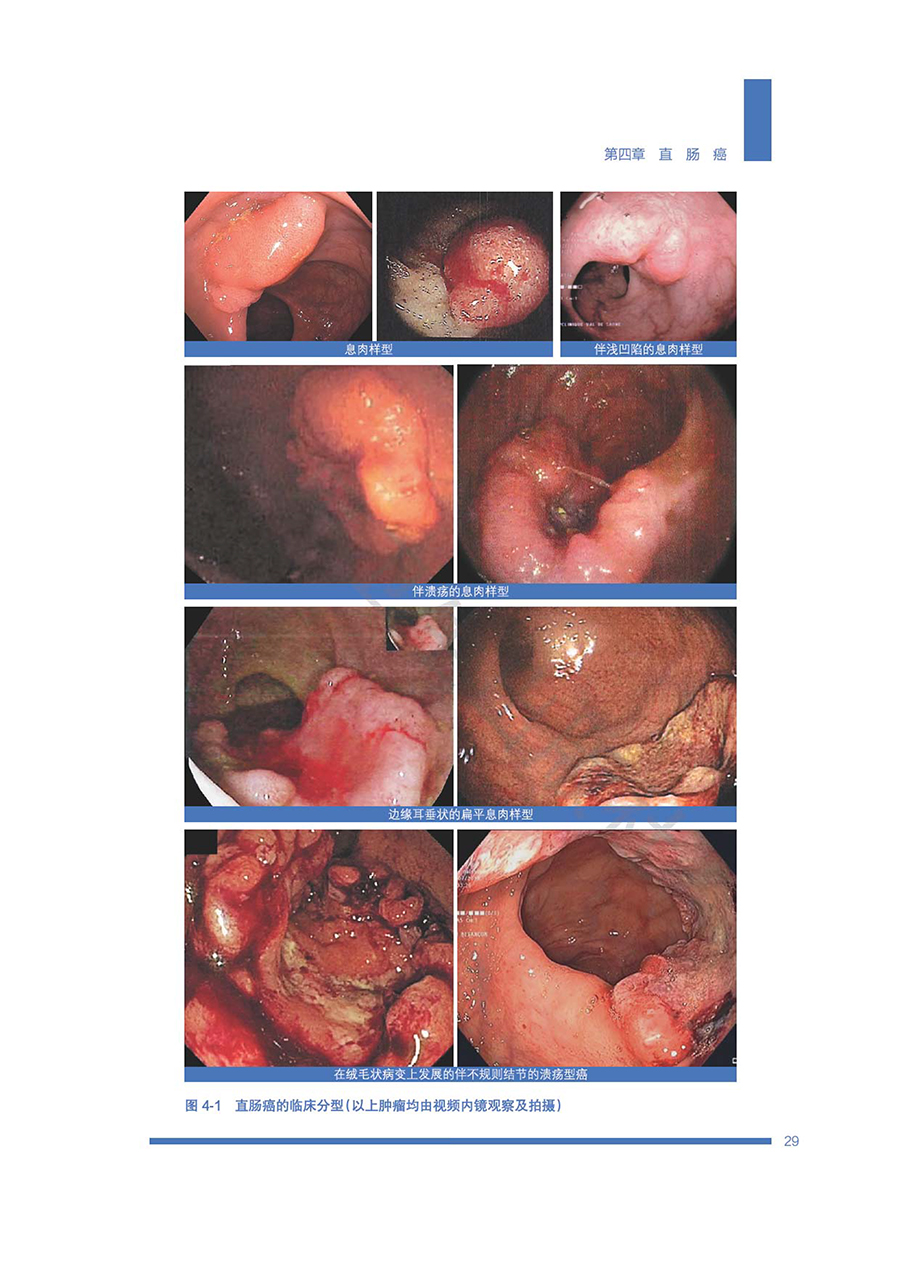

本书共8章,以新一代50kV浅层X线治疗机为基础,系统论述50kV浅层X线治疗机的放射物理基础、治疗原理,阐述其高剂量率少分次数治疗的临床优势,以及在直肠癌保肛治疗、乳腺癌及腹部肿瘤术中放疗、皮肤癌及皮肤良性疾病中的临床应用,特别是低位直肠癌和老年直肠癌治疗重点良好效果及高级别循证医学证据。该放射治疗设备不同于现代加速器和粒子治疗设备,体积小,移动方便,直视操作,防护要求低,适用机构范围广,为中国目前及未来的高肿瘤疾病负荷形势提供了经济有效的临床解决方案,同时能大幅度提高肿瘤患者的生活质量。